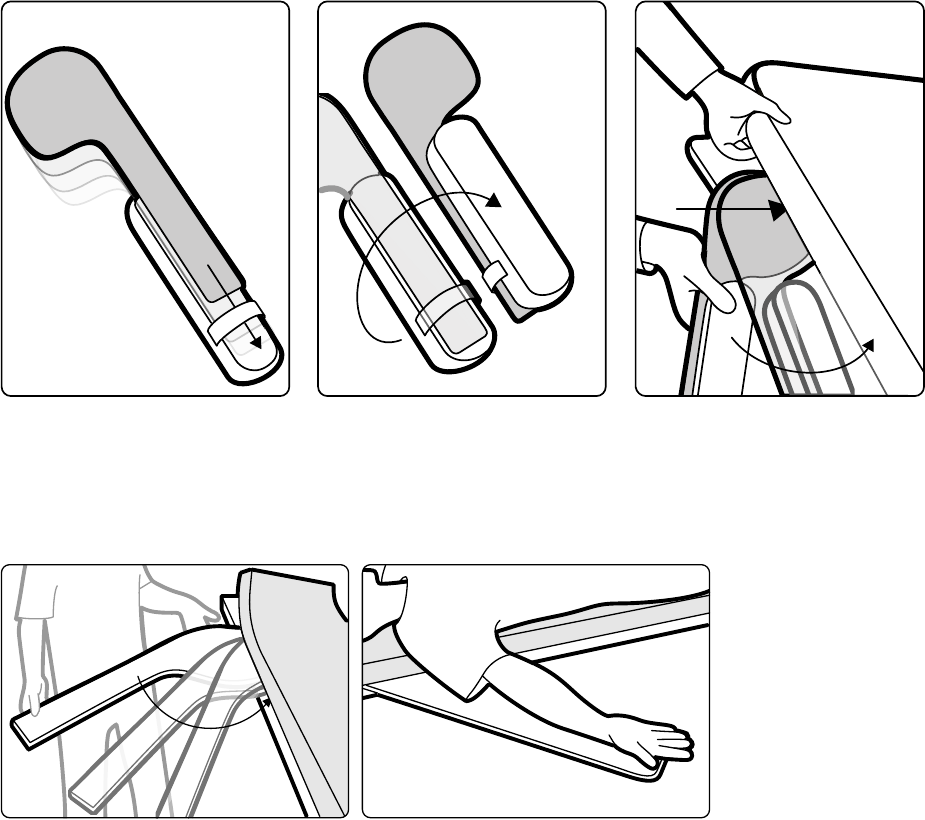

5.9.8 Stosowanie jałowych okryć.................................................................................... 66

5.10.3 Zakładanie jałowych i jednorazowych osłon.......................................................... 72